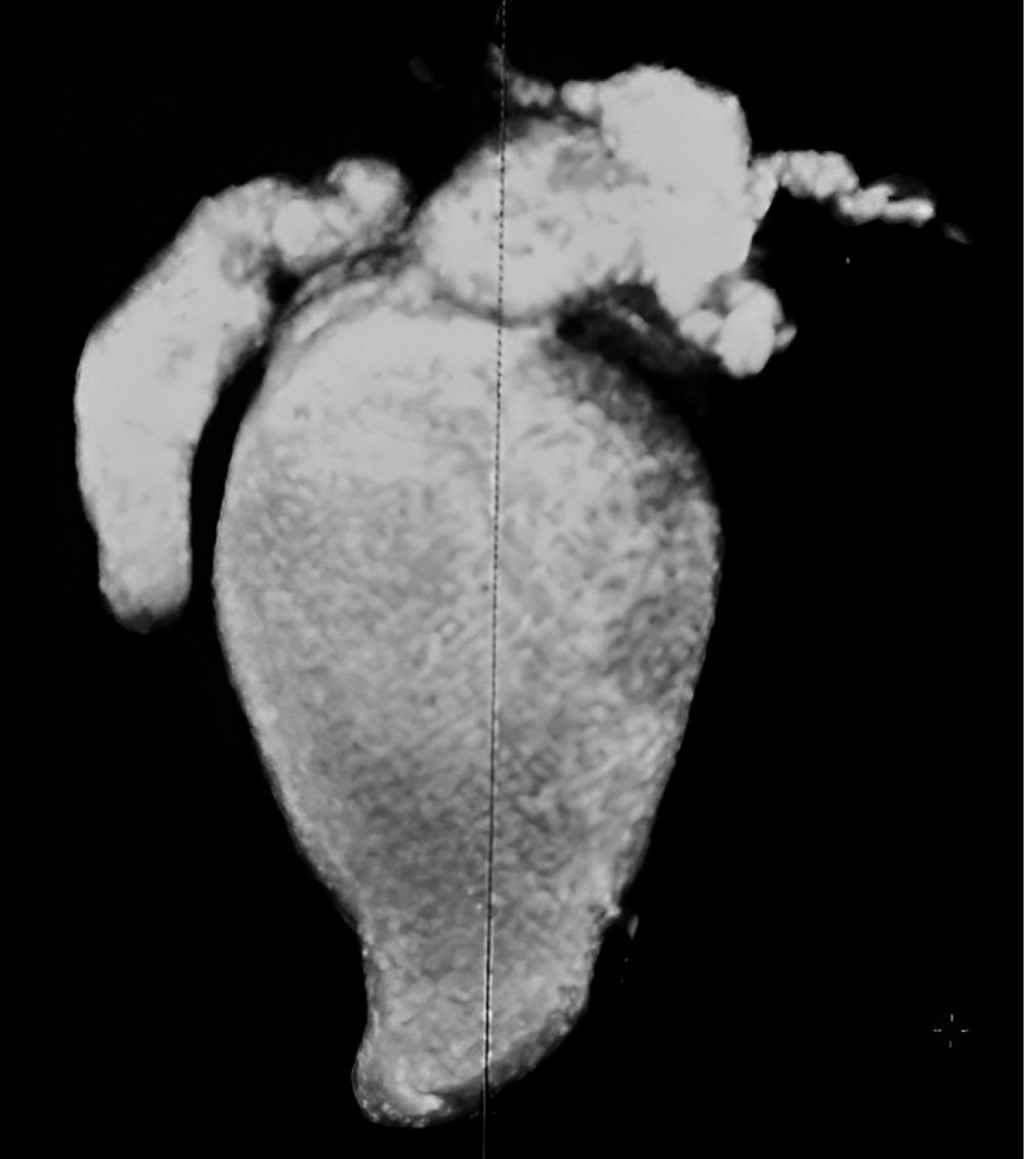

En su localidad de origen se le realizó una ecografía hepática y de vías biliares (EHVB), interpretando la presencia de un quiste hepático. Después, en Pachuca, Hidalgo, se llevó a cabo una CR-M, la cual confirmó el diagnóstico de quiste de colédoco por parte del cirujano general, quien la remitió al HCGFAA por falta de recursos. Se realizaron análisis de laboratorio (Tabla 1) y se llevó a cabo una nueva CR-M (Figuras 3 y 4) que mostró un QC-IVA-Todani-modificada (Figura 2).

Hallazgos: vesícula biliar atrófica sin presencia de cálculos biliares, quiste de 7.6 mm en el conducto cístico, dilatación sacular de la vía biliar intra y extrahepática con un diámetro de 18 mm en el hepático derecho, 15 mm en el hepático izquierdo y una zona de confluencia de 33 mm (carina). Se observó una máxima dilatación del colédoco de 70 mm, colédoco distal de 23 mm y el conducto de Wirsung con dimensiones normales.